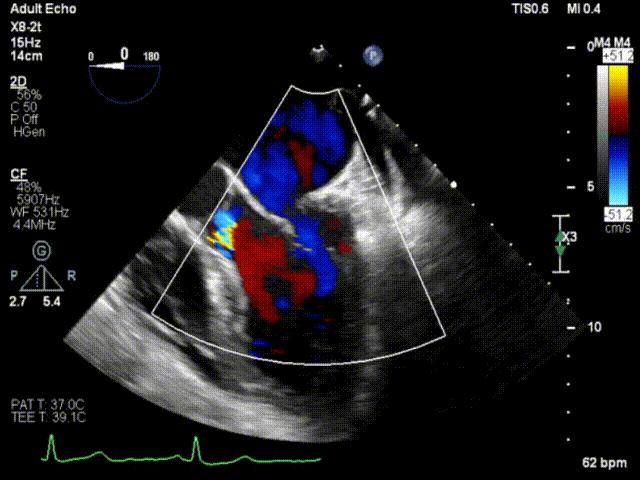

患者男性,63岁,主诉间歇性心悸5年,加重3月。门诊以“二尖瓣关闭不全”收入西京医院。术前超声提示:二尖瓣关闭不全,前叶26mm,后叶22mm,二尖瓣腱索断裂,后叶P1区及部分P2区脱垂,脱垂高度9mm,脱垂宽度15mm,舒张期瓣口面积约6.8cm²,反流束位置位于1区偏2区,Carpentier分型Ⅱ型,心功能Ⅳ级(NYHA分级)。

术前超声心动图